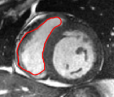

V-B Ventricle Segmentation: Comparison of Three Registration Schemes

In this experiment, we focus on real cardiac MRI data and compare registration methods used for segmentation of the LV and RV. We visually compare the tracking results given by our method to (M1) registration of only the interior of current estimate of the ventricle to a subset of next image (to show whole image registration is needed), and to (M2) standard full image registration with global smoothness. M1 is achieved by computing just the inside velocity with Neumann boundary conditions on (normal constraint does not apply in M1). The best results with respect to ground truth are chosen by choosing the optimal parameter in all methods. Results on LV and RV tracking for a full cardiac cycle are given in Figure 6 for the LV and Figure 7 for the RV. Registering only the organ (M1) results in errors (as the background registration is helpful in restricting undesirable registrations of the foreground). Globally smooth registration (M2) smooths motion from irrelevant background structures into the ventricles, which results in drifting from the desired boundary. Our method, which smooths within regions with satisfying the physical constraint, is able to achieve the most accurate results.